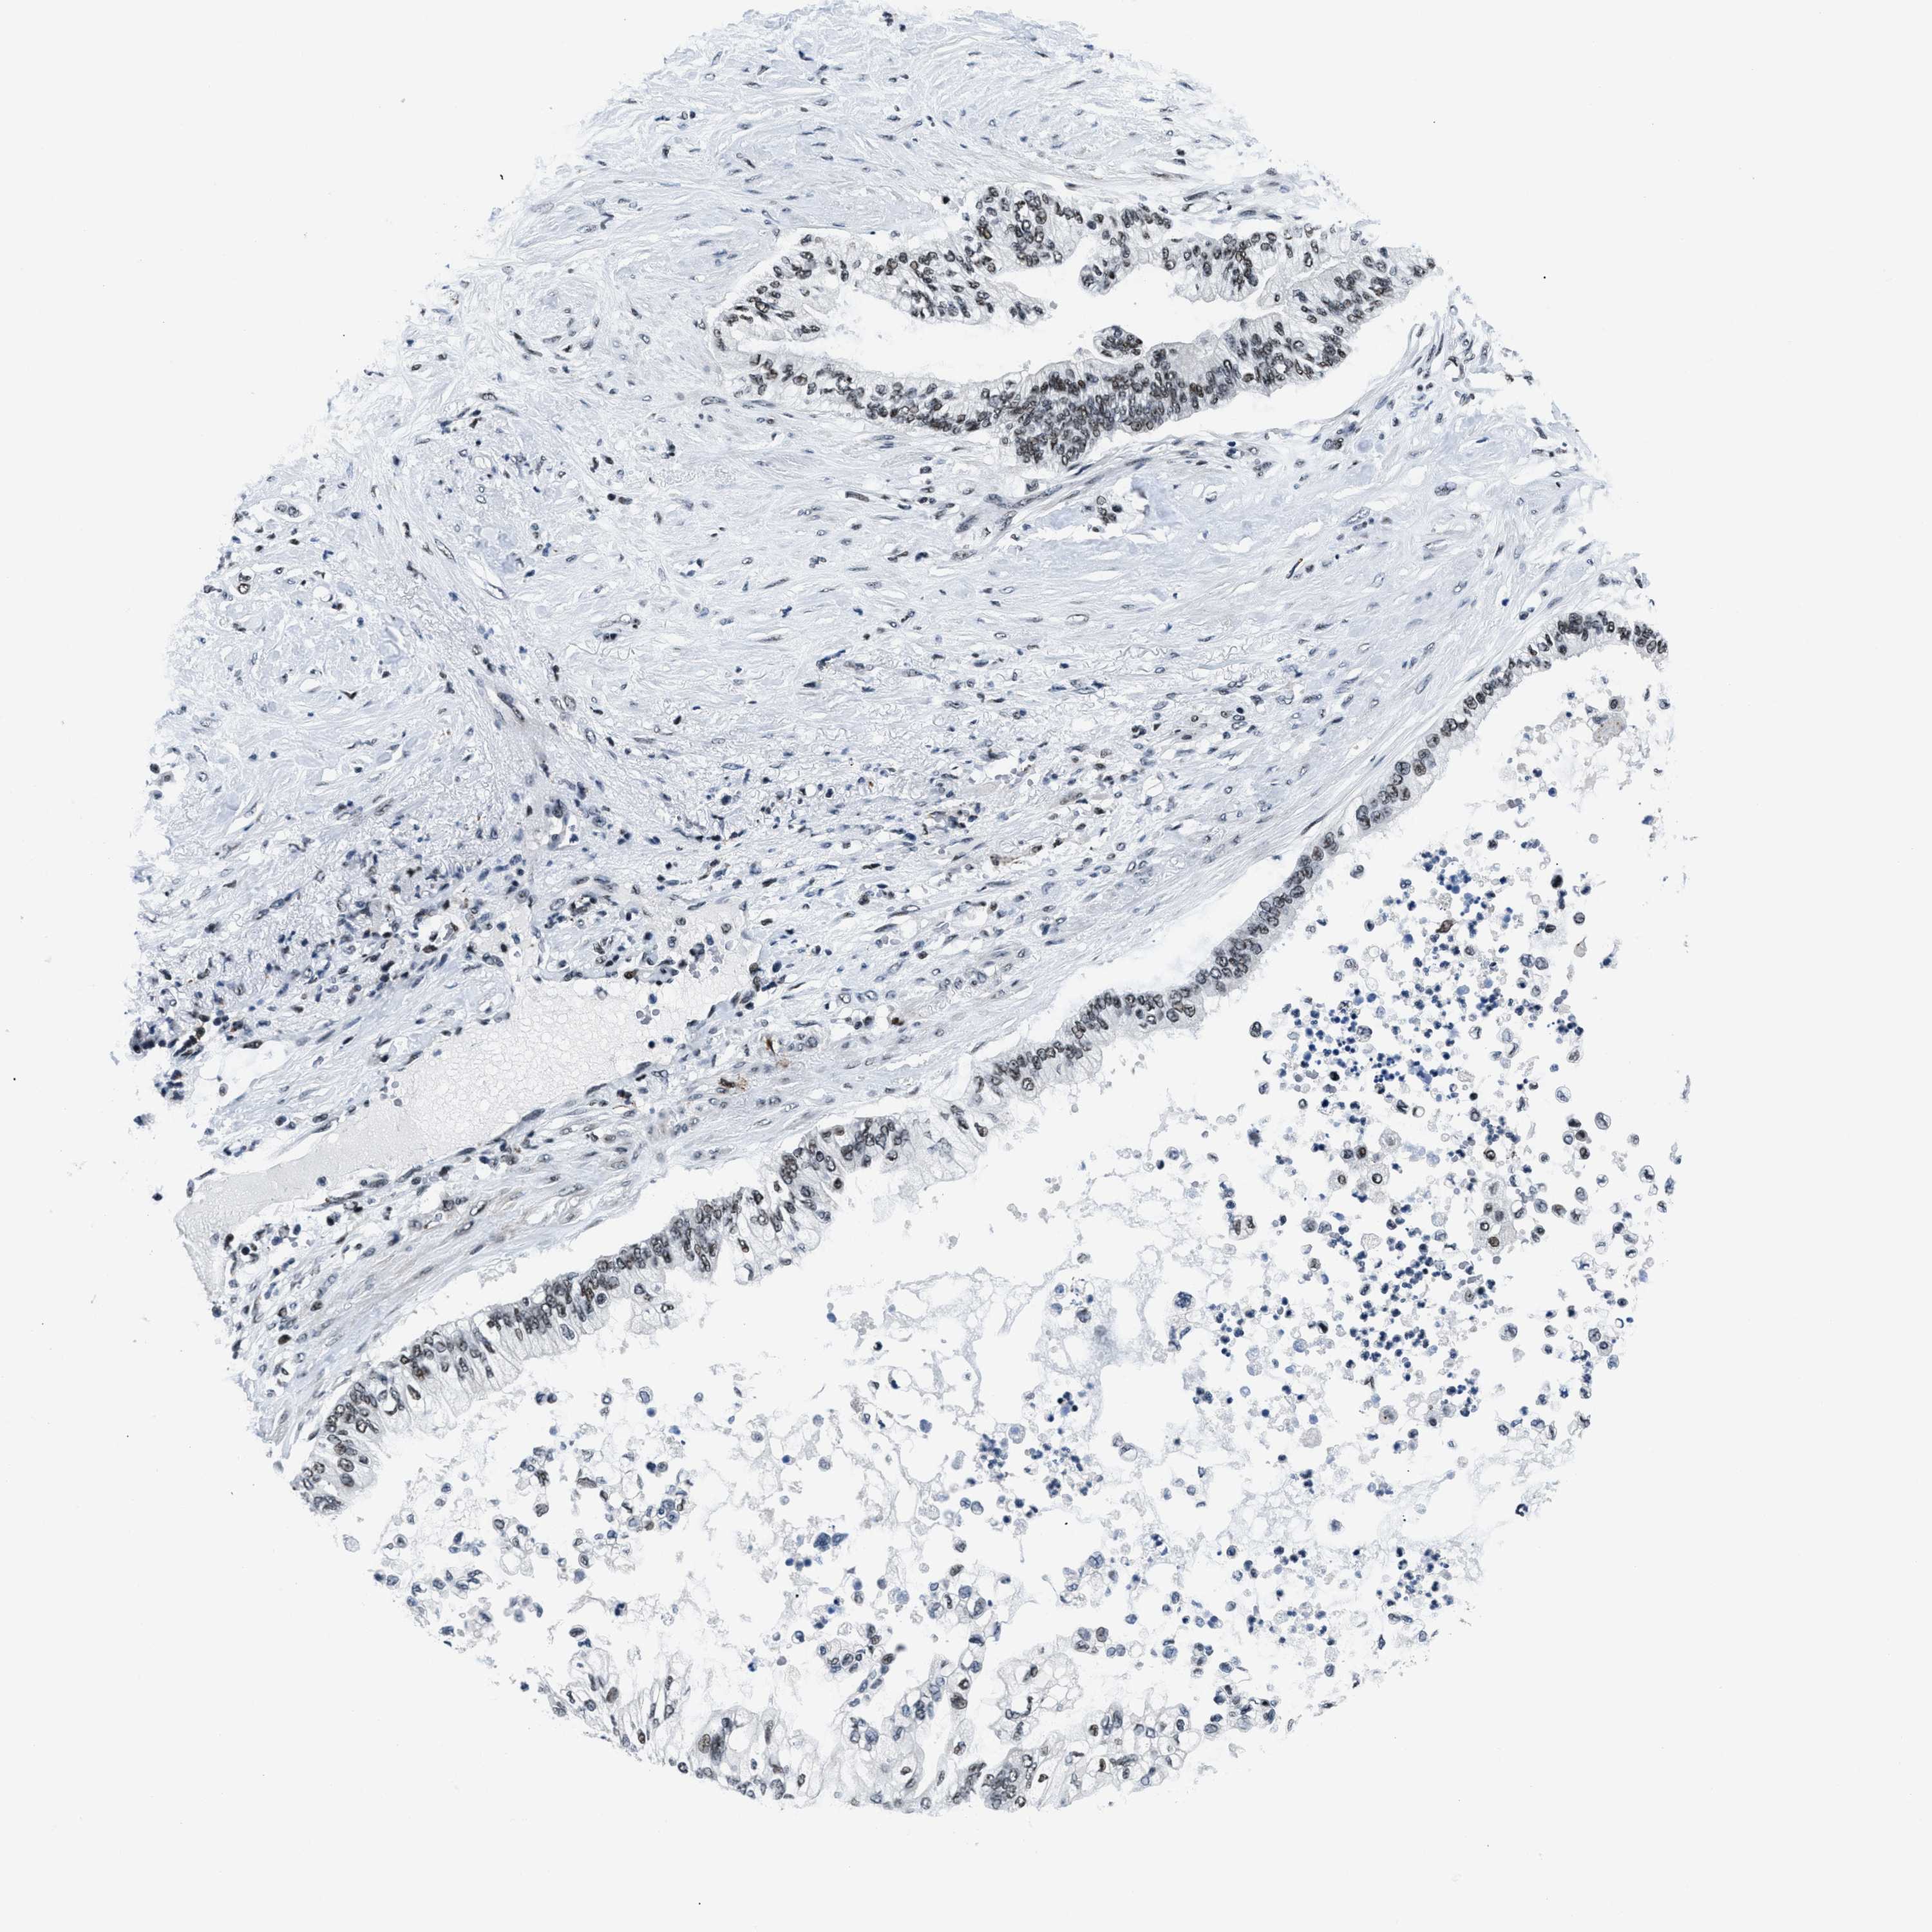

PANCREATIC CANCER - Protein expressioni

A mouse-over function shows sample information and annotation data. Click on an image to view it in a full screen mode. Samples can be filtered based on level of antibody staining by selecting one or several of the following categories: high, medium, low and not detected. The assay and annotation is described here.

Note that samples used for immunohistochemistry by the Human Protein Atlas do not correspond to samples in the TCGA dataset.

Antibody stainingi

Antibody staining in the annotated cell types in the current human tissue is reported as not detected, low, medium, or high, based on conventional immunohistochemistry profiling in selected tissues. This score is based on the combination of the staining intensity and fraction of stained cells.

Each image is clickable and will lead to virtual microscopy that enables deeper exploration of all samples and also displays staining intensity scores, fraction scores and subcellular localization as well as patient and tissue information for each sample.

Antibody HPA018248

Antibody HPA019127

Antibody CAB009196

Staining

High

Medium

Low

Not detected

Intensity

Strong

Moderate

Weak

Negative

Quantity

>75%

75%-25%

<25%

None

Location

Nuclear

Cytoplasmic/membranous

Cytoplasmic/membranous,nuclear

Adenocarcinoma, NOS

Adenocarcinoma, metastatic, NOS